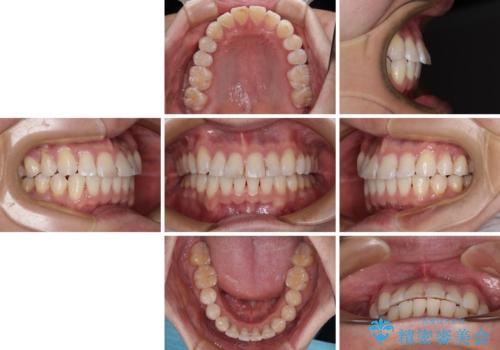

- 以前矯正治療を行ったものの、思い通りの仕上がりではなく、更には後戻りが気になってきたとのことで来院された患者様です。

上顎右側の第一小臼歯が動きにくい歯であり、以前矯正治療を行った際に傾斜した位置のまま終了したことと、それに伴い後戻りで歯列が波打っているようになっていることを大変気にしていらっしゃいました。

咬合平面改善のため、アンカースクリューを多用し、ワイヤー装置にて矯正治療を行うこととしました。

動きにくい歯はやはり動きにくく、咬み合わせ改善に時間を要しましたが、患者様には大変満足していただけました。